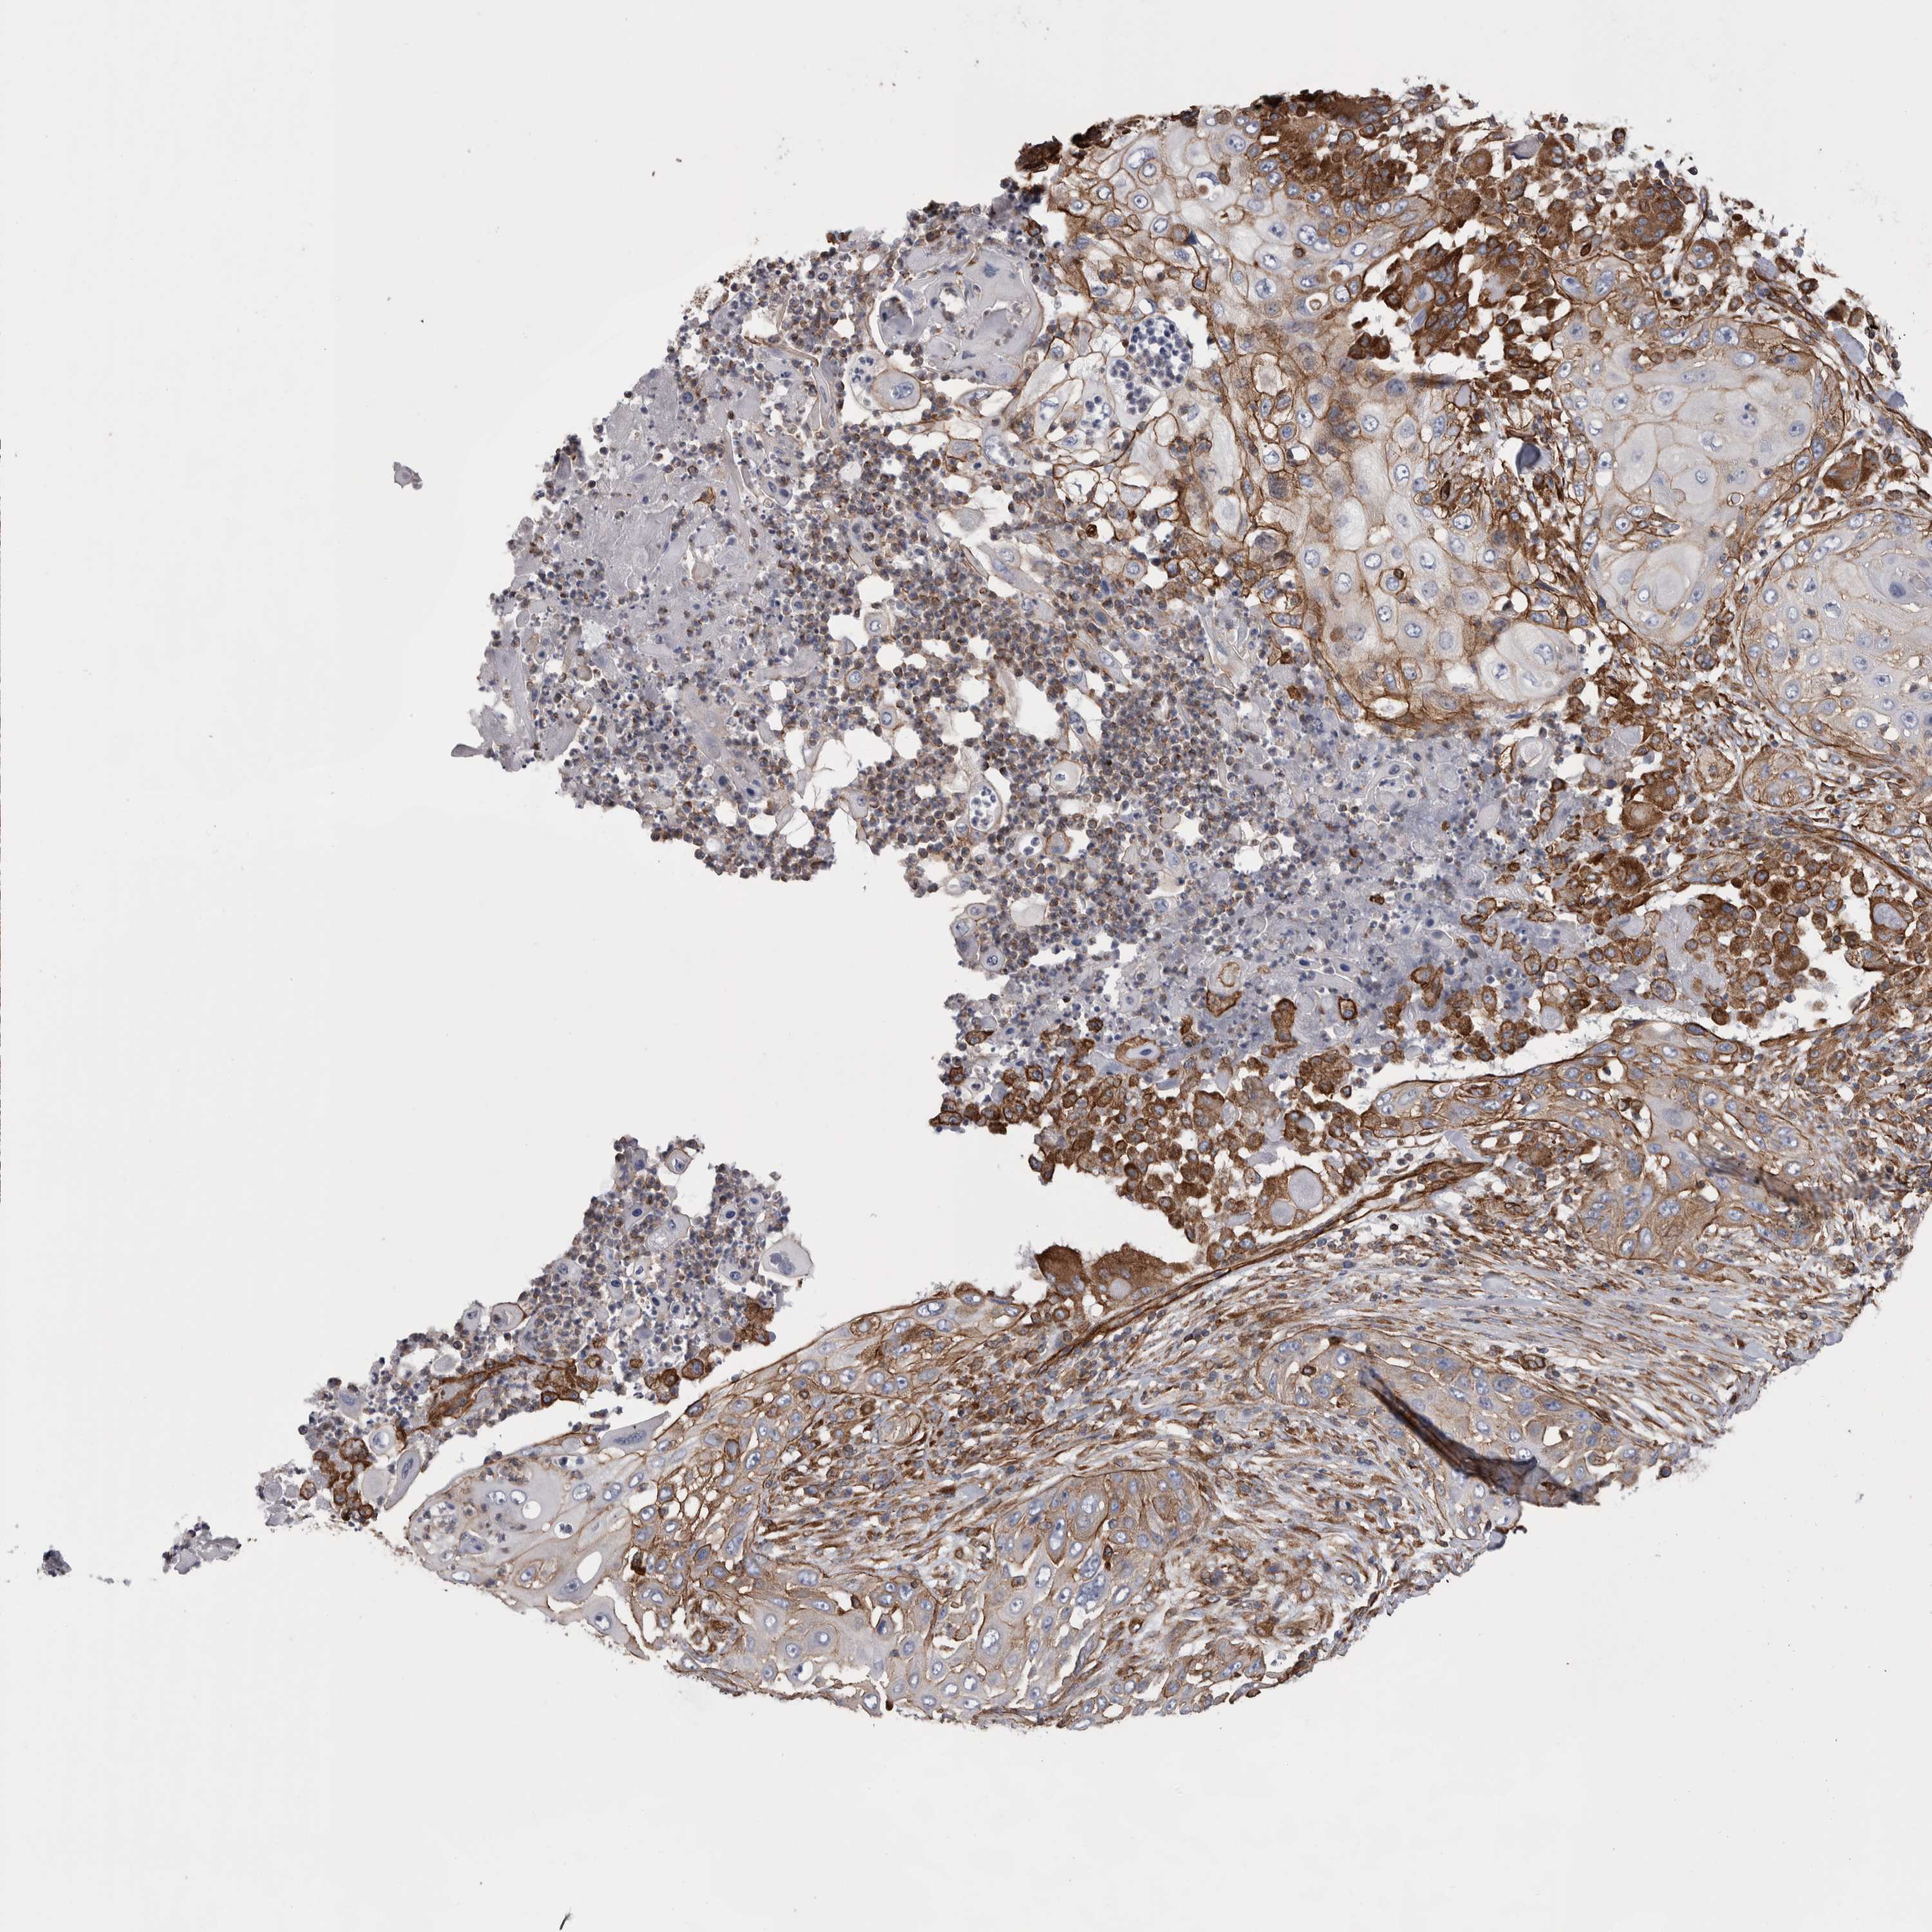

Basal cell and squamous cell cancer

SKIN CANCER - Protein expressioni

A mouse-over function shows sample information and annotation data. Click on an image to view it in a full screen mode. Samples can be filtered based on level of antibody staining by selecting one or several of the following categories: high, medium, low and not detected. The assay and annotation is described here.

Antibody stainingi

Antibody staining in the annotated cell types in the current human tissue is reported as not detected, low, medium, or high, based on conventional immunohistochemistry profiling in selected tissues. This score is based on the combination of the staining intensity and fraction of stained cells.

Each image is clickable and will lead to virtual microscopy that enables deeper exploration of all samples and also displays staining intensity scores, fraction scores and subcellular localization as well as patient and tissue information for each sample.

Antibody HPA020192

Antibody HPA024127

Staining

High

Medium

Low

Not detected

Intensity

Strong

Moderate

Weak

Negative

Quantity

>75%

75%-25%

<25%

None

Location

Nuclear

Cytoplasmic/membranous

Cytoplasmic/membranous,nuclear

Squamous cell carcinoma, NOS

Squamous cell carcinoma, metastatic, NOS